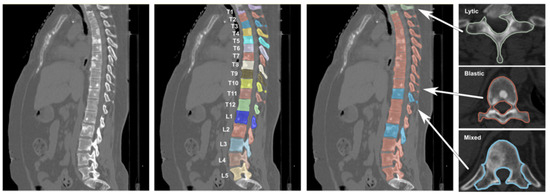

The rapid development of Generative Adversarial Networks (GANs) has transformed medical image processing, enabling realistic image synthesis, augmentation, and restoration. This study presents a comparative evaluation of three representative GAN architectures, Pix2Pix, SPADE GAN, and Wasserstein GAN (WGAN), across multiple medical imaging tasks,

The rapid development of Generative Adversarial Networks (GANs) has transformed medical image processing, enabling realistic image synthesis, augmentation, and restoration. This study presents a comparative evaluation of three representative GAN architectures, Pix2Pix, SPADE GAN, and Wasserstein GAN (WGAN), across multiple medical imaging tasks, including segmentation, image synthesis, and enhancement. Experiments were conducted on three benchmark datasets: ACDC (cardiac MRI), Brain Tumor MRI, and CHAOS (abdominal MRI). Model performance was assessed using Fréchet Inception Distance (FID), Peak Signal-to-Noise Ratio (PSNR), Structural Similarity Index (SSIM), Dice coefficient, and segmentation accuracy. Results show that SPADE-inpainting achieved the best image fidelity (PSNR ≈ 36 dB, SSIM > 0.97, Dice ≈ 0.94, FID < 0.01), while Pix2Pix delivered the highest segmentation accuracy (Dice ≈ 0.90 on ACDC). WGAN provided stable enhancement and strong visual sharpness on smaller datasets such as Brain Tumor MRI. The findings confirm that no single GAN architecture universally excels across all tasks; performance depends on data complexity and task objectives. Overall, GANs demonstrate strong potential for medical image augmentation and synthesis, though their clinical utility remains dependent on anatomical fidelity and dataset diversity.